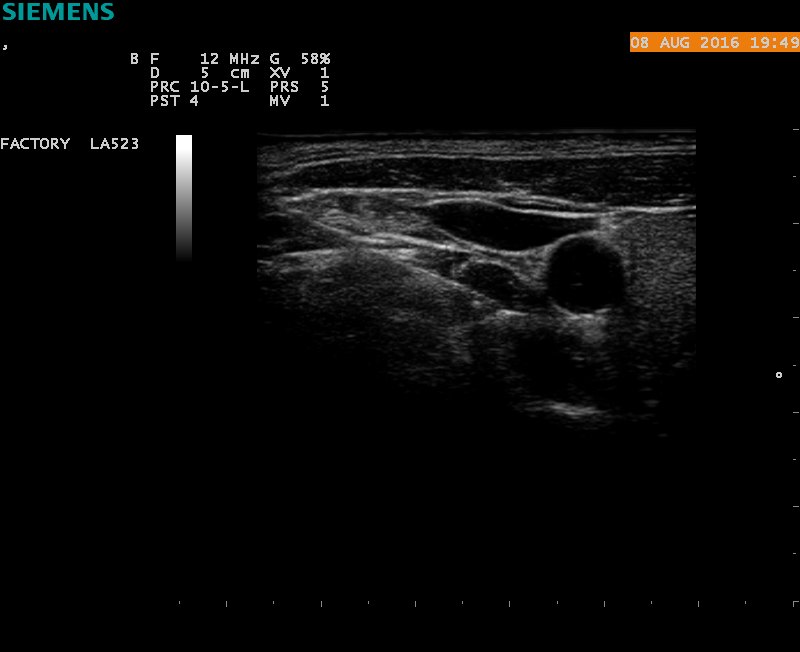

病人采用侧卧位,患侧在上,常规吸氧,心电监护,消毒铺巾,超声高频探头